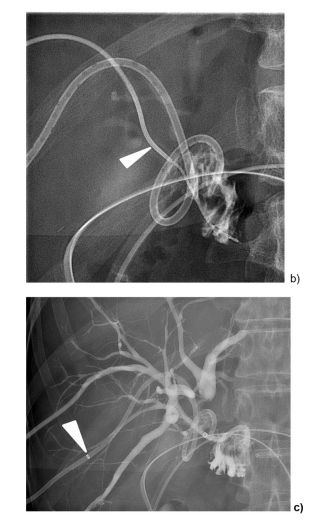

Post image Post image Post image

2/5 Study Details:

- Participants: 4 patients (mean age 56)

- Background: Right posterior bile duct exclusion and bile leakage after liver/pancreatic surgery or liver transplant

- Method: Fluoroscopy-guided PBNA followed by PTBD

#Hepatology

21.03.2025 12:00 — 👍 0    🔁 0    💬 1    📌 0

3/5 Key Findings:

- Technical success: 100%

- PTBDs removed median of 65 days post-procedure

- Median follow-up: 2.8 years

- Outcomes: No bile leakages or re-occlusions observed

- Complications: None reported

#PatientOutcomes #Safety

4/5 📌 Conclusion: In this small study, PBNA achieved 100% technical success with no reported complications, bile leakages, or re-occlusions during a median follow-up of 2.8 years.

Full study: doi.org/doi:10.1007...

#BiliarySurgery #Transplantation #MedTwitter

1/5 🚨 100% technical success in performing percutaneous biliary neo-anastomosis (PBNA) with fluoroscopy guidance!👇

Check out this recent study from CVIR exploring the safety and effectiveness of PBNA for challenging biliary conditions 🧵

#BiliaryIntervention #InterventionalRadiology